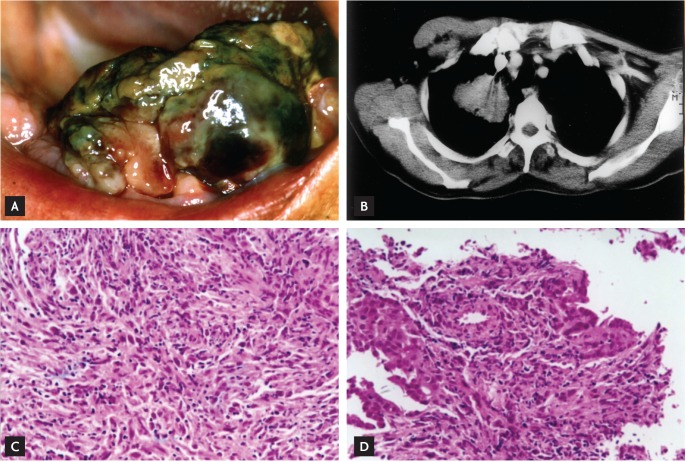

Figure 1

Clinical, imaging, and microscopic findings. (A) A soft 3 × 4-cm pedunculated mass with a necrotic and ulcerated surface on the floor of the mouth. (B) A 5 × 5-cm mass on the apical segment of the right lower lobe and hilar lymphadenopathy on chest computed tomography. (C, D) A storiform pattern of plump spindled cells characterized by cellular pleomorphisms with numerous mitotic figures (H&E, ×100) in masses excised from the floor of the mouth and lung.

A 62-year-old man presented to our clinic complaining of a sublingual mass and left shoulder pain for 3 months. Analysis of his medical history was noncontributory. On physical examination, a soft 3 × 4-cm pedunculated mass with a necrotic and ulcerated surface was identified on the floor of the mouth (Fig. 1A). The remainder of the clinical examination, including examinations of the patient's respiratory system, revealed no abnormalities. A chest radiograph revealed a 5-cm lobulated mass in the right upper lobe of the lung. A subsequent chest computed tomography scan revealed a 5 × 5-cm mass on the apical segment of the right lower lobe and hilar lymphadenopathy (Fig. 1B). Following diagnosis, the patient underwent a bronchoscopic biopsy to remove the mass, along with an incisional biopsy of the mass in the oral cavity. Morphologically, the excised masses were composed of pleomorphic spindled tumor cells resembling a malignant fibrous histiocytoma (Fig. 1C and 1D). By immunohistochemical staining, the malignant cells were diffusely strongly positive for vimentin and focally positive for cytokeratin (Fig 2). However, the malignant cells were negative for S-100 protein and HMB45. Following surgery, the patient received radiation therapy on the oral cavity, in addition to palliative chemotherapy; however, the response to these therapies was poor, and he died 4 months after diagnosis.